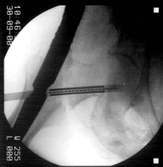

Das Ergebnis ist eine Fehlplazierung der Schenkel- halsschraube Diese korrekte Lage wurde mit dem neuartigen Zielgerät erreicht. Das neue Zielgerät läßt sich leicht auf dem Obturator befestigen und zielt sowohl in der Aufsicht, als auch in der Seitaufnahme. Links ist die falsche Position und rechts durch Drehung des Zielgerätes die korrekte Position zu sehen. Liegen die drei Drähte nun zu weit Proximal, muß der Nagel wieter nach distal geschoben werden.

Position des Gerätes in seitlicher Lage ergibt beim Röntgen die folgenden Aufnahmen. Der geriffelte Draht liegt nicht zwischen den zwei glatten Drähten. Bewegen des Zielgerätes ergibt das erforderliche Bild. Sollten die so positionierten Drähte sich nicht über dem Kopf abbilden, muß der Nagel gedreht werden. Auf diese Weise erreicht man die korrekte Lage der Schenkelhalsschraube in die Mitte des Kopfes, ein Auswandern der Schraube ist so unmöglich.